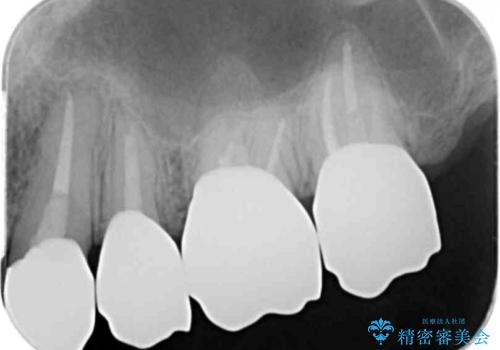

ここの歯の状態を精密に検査し、根管治療、セラミック治療、インプラント治療を含む総合的な歯科治療を計画します。

- 242万円(ジルコニアクラウン・仮歯×7本 インプラント×2本)費用は治療当時の料金となります